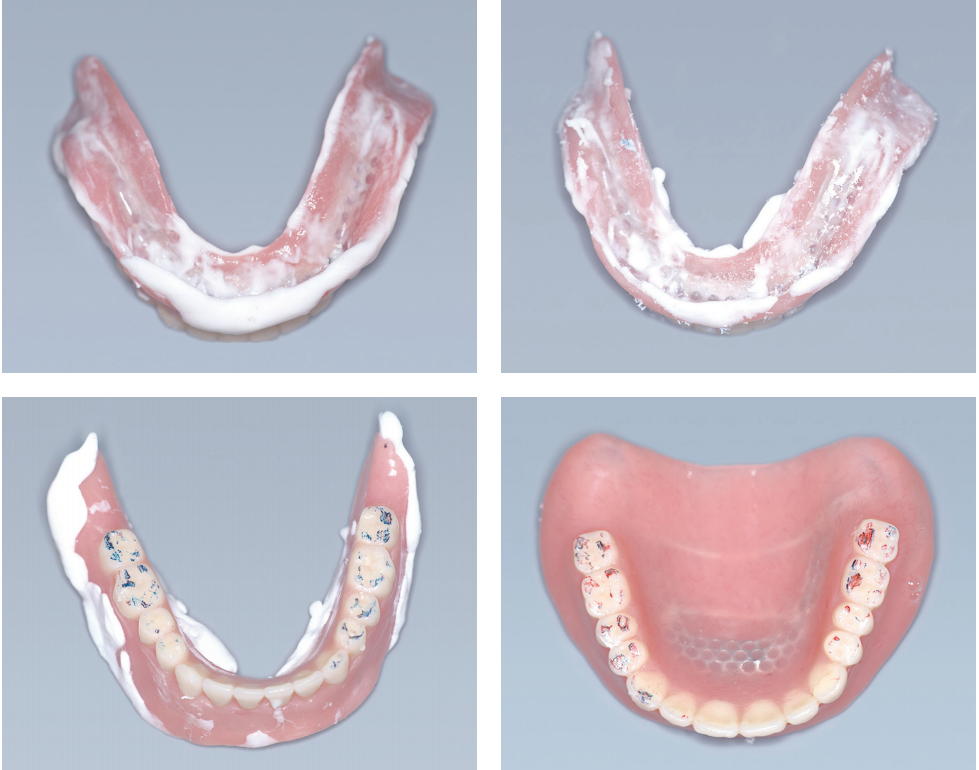

3. Wax Denture 시적

Kelly’ combinaton syndrome 때문에 하악 전치가 유난히 돌출되어 보이고 하악 구치부에서 통증을 호소하였다.

상악 전치부 배열 상태는 양호하다. 하악 전치부가 치은 부위까지 보인다. VD를 하악에서만 3mm 낮추기로 하였다.

Kelly’ combination syndorme

상악이 무치악 상태이고 하악은 전치부만 남아 있는 상태가 오랫동안 지속되었을 때 구강 내에서 일어나는 변화들이다. 다음 그림에서 보이는 것처럼 여러 부위에서 퇴행성 변화가 일어난다.